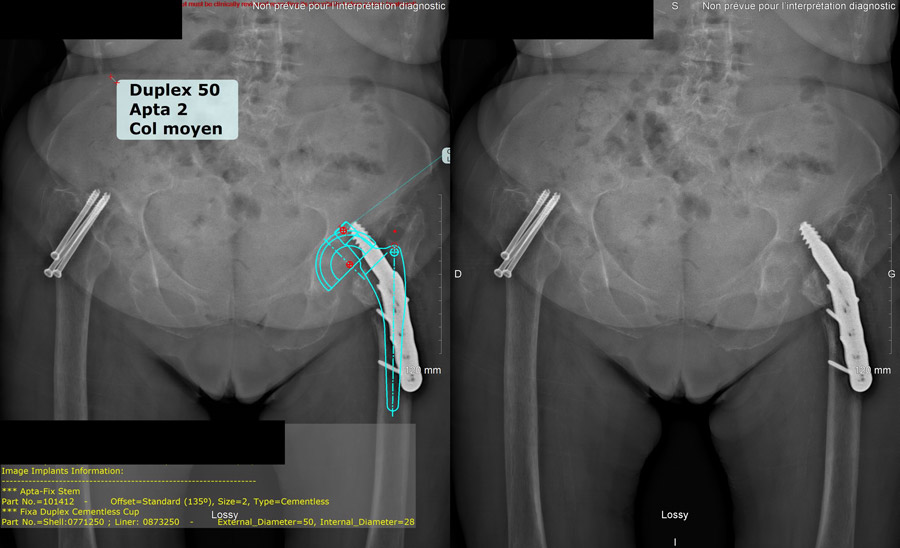

Hip planification

Hip planification of the right hip